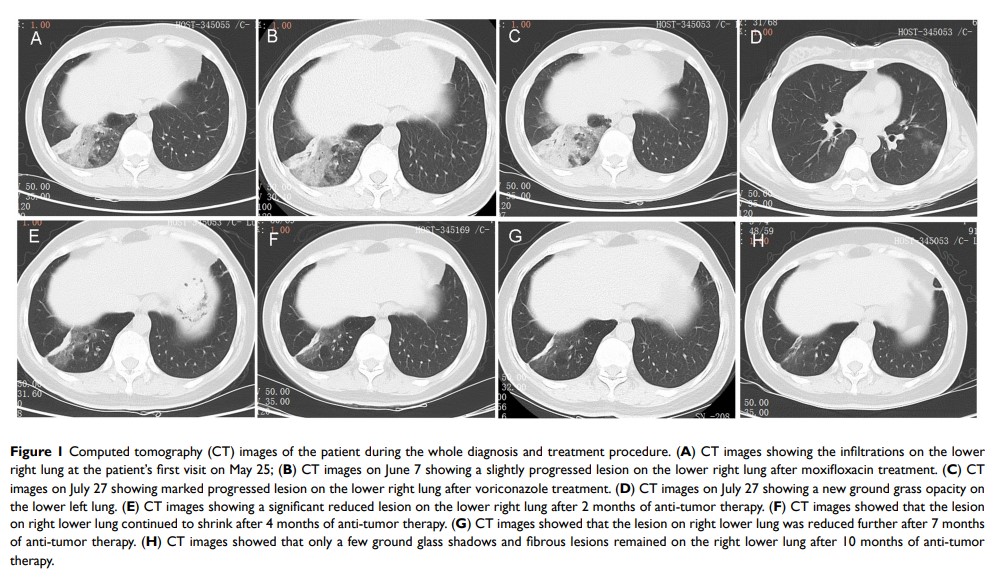

KIF5B-EGFR 融合:肺腺癌中新的 EGFR 突变